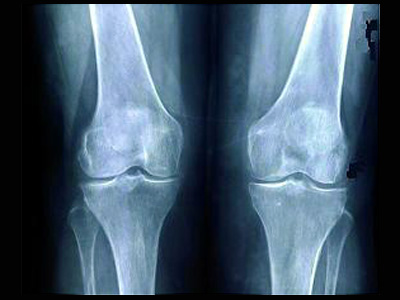

Uma equipe médica do Into, especialista em cirurgias de joelhos, foi deslocada para Manaus, onde os 25 procedimentos previstos para a semana englobam pacientes que necessitam de artroplastia primária – primeira prótese – e cirurgia de revisão – para substituir o implante. O mutirão em Manaus faz parte do Projeto Suporte, que leva profissionais de saúde para regiões em que a oferta por cirurgias ortopédicas é baixa.